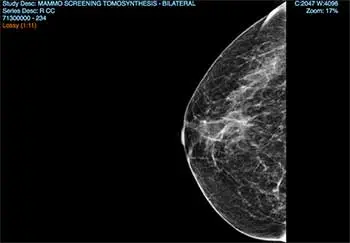

mammogram image

imaging results of a breast after getting a mammogram

Because you have dense breast tissue, you have to get 3D mammograms, or tomosynthesis. This sounds extra scary, but really, it’s not. It’s kind of magic, really, that this kind of technology exists.

As the efficient but gentle woman arranges you into position for the scan, you think about all the women in the past who died from breast cancer without even knowing they had it. If you’d been born just 20 years earlier, you wouldn’t have access to a machine with the power to detect cancer in your kind of breasts. You realize how lucky you are to be here.